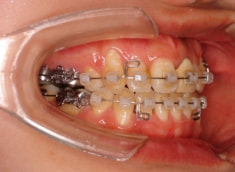

治療開始時

治療開始から約1年後